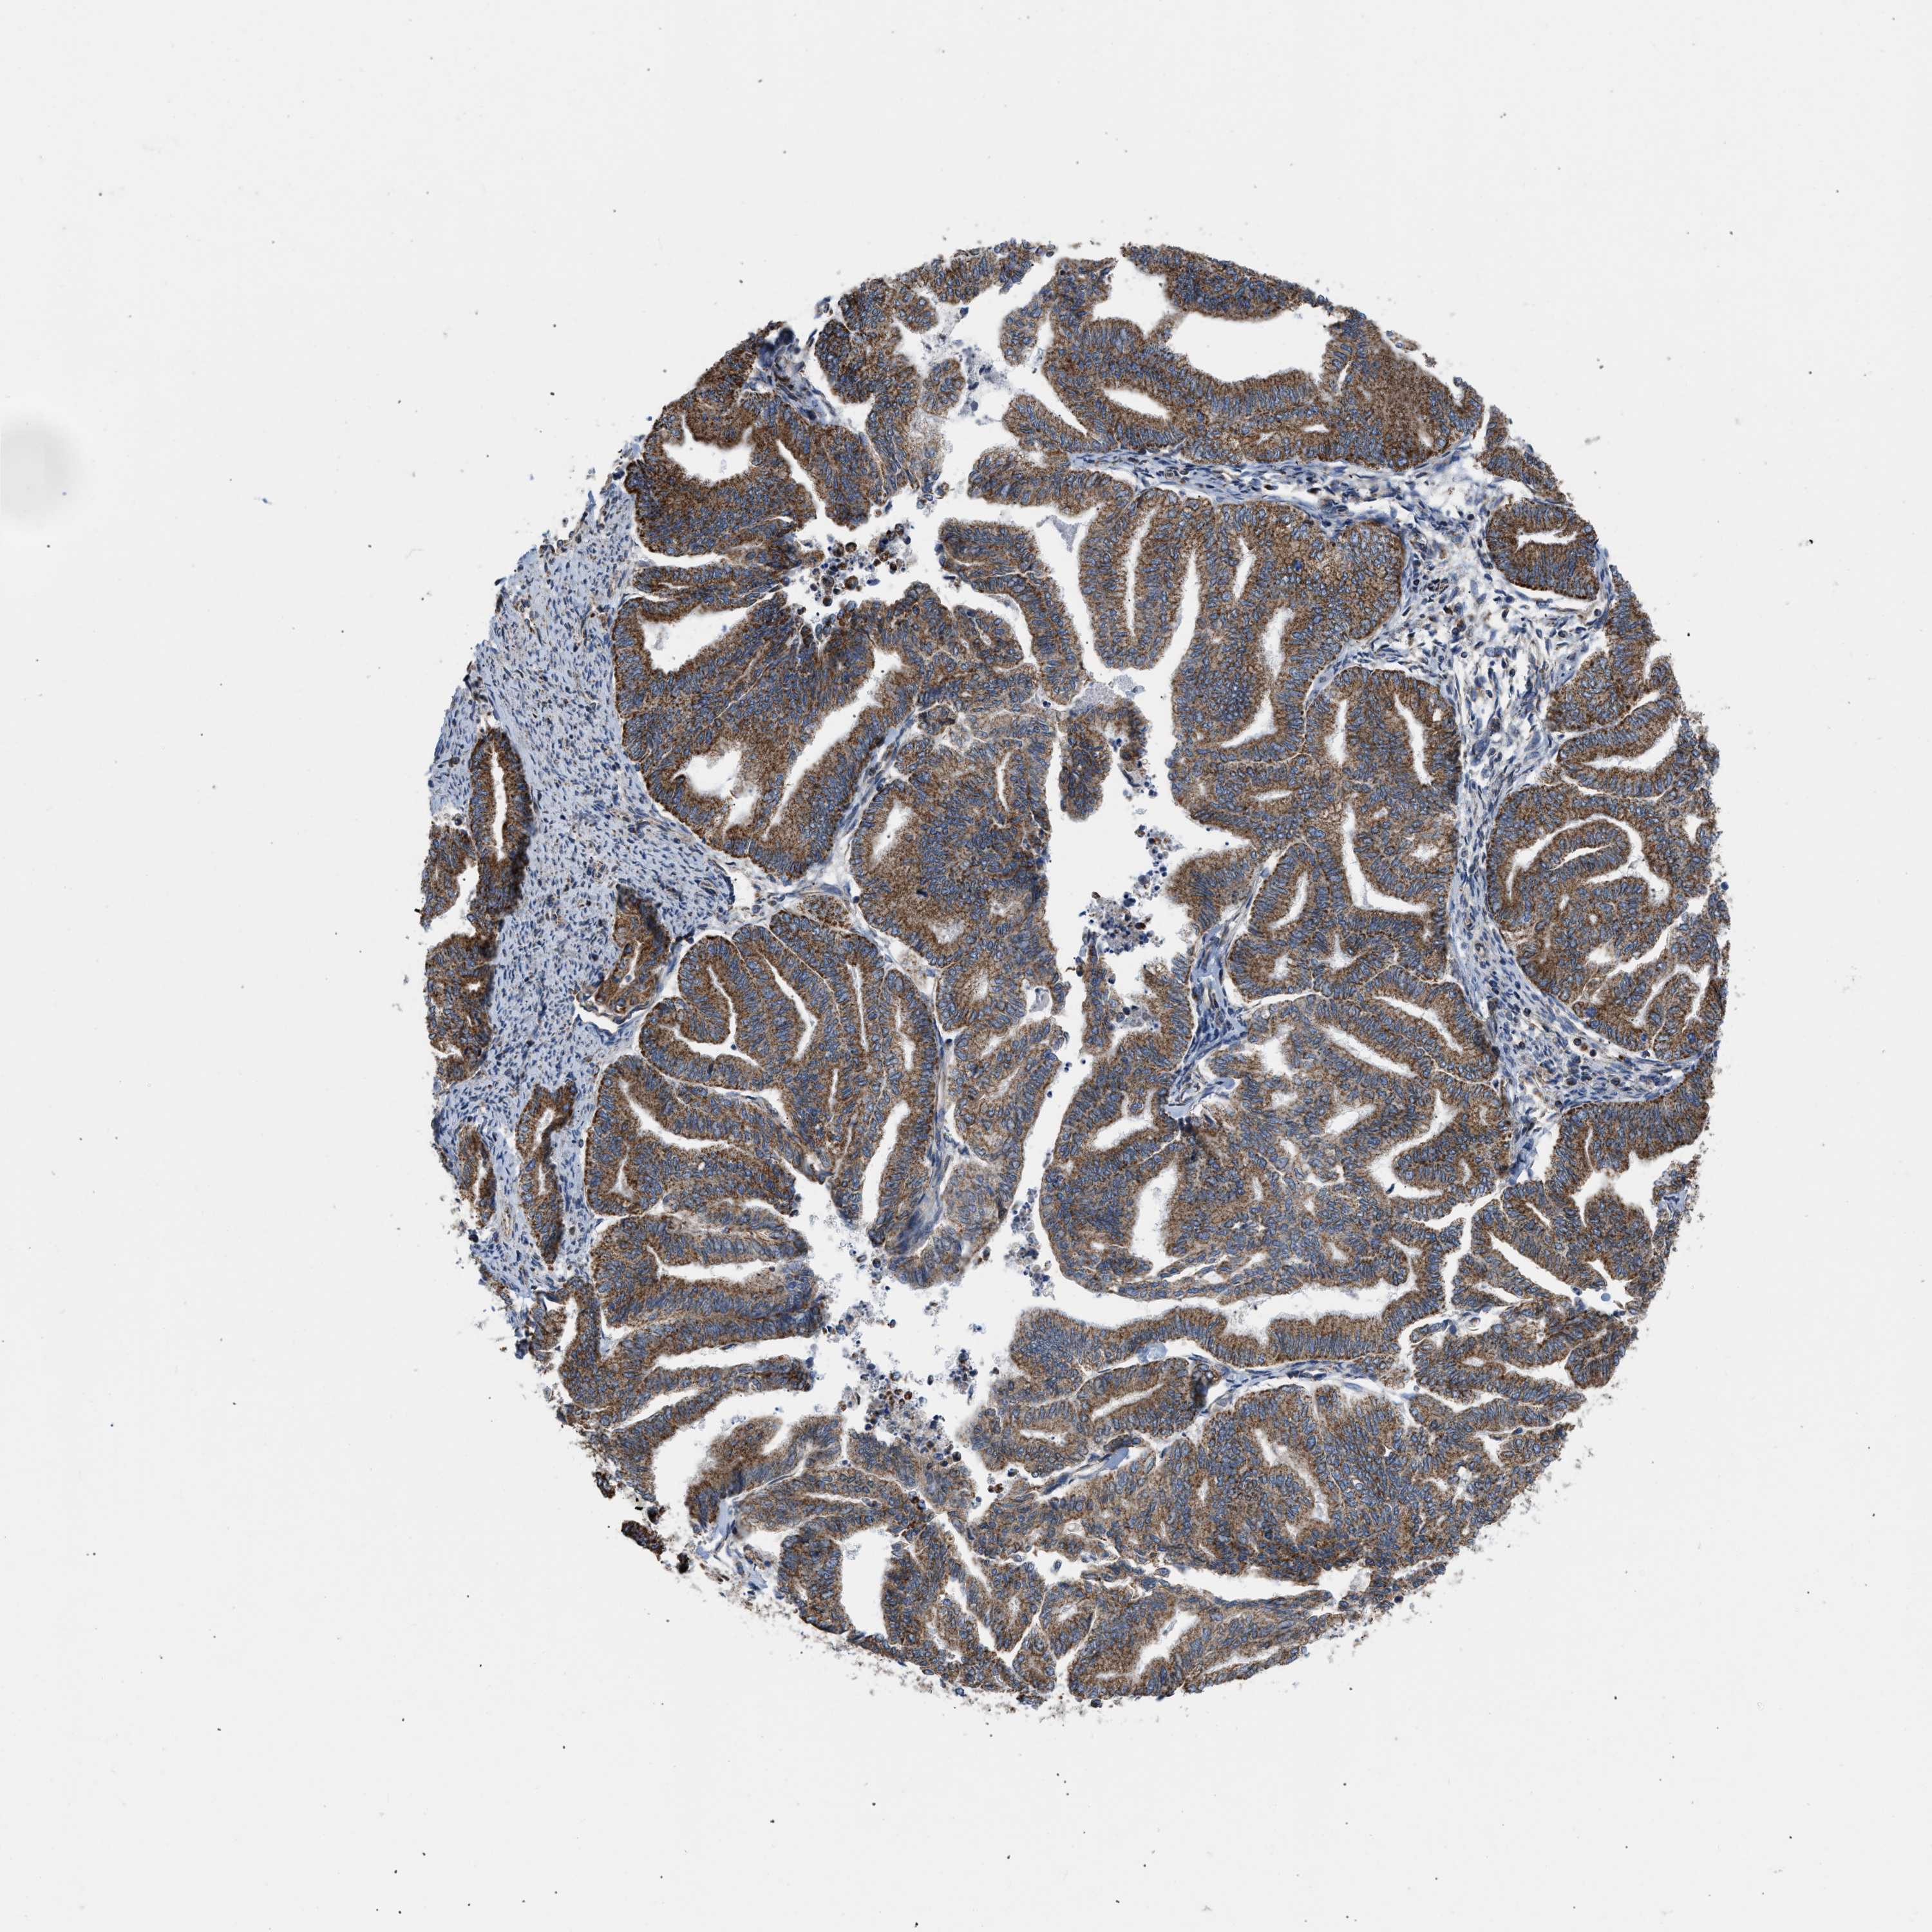

ENDOMETRIAL CANCER - Protein expressioni

A mouse-over function shows sample information and annotation data. Click on an image to view it in a full screen mode. Samples can be filtered based on level of antibody staining by selecting one or several of the following categories: high, medium, low and not detected. The assay and annotation is described here.

Note that samples used for immunohistochemistry by the Human Protein Atlas do not correspond to samples in the TCGA dataset.

Antibody stainingi

Antibody staining in the annotated cell types in the current human tissue is reported as not detected, low, medium, or high, based on conventional immunohistochemistry profiling in selected tissues. This score is based on the combination of the staining intensity and fraction of stained cells.

Each image is clickable and will lead to virtual microscopy that enables deeper exploration of all samples and also displays staining intensity scores, fraction scores and subcellular localization as well as patient and tissue information for each sample.

Antibody HPA003279

Antibody HPA003360

Antibody CAB019303

Staining

High

Medium

Low

Not detected

Intensity

Strong

Moderate

Weak

Negative

Quantity

>75%

75%-25%

<25%

None

Location

Nuclear

Cytoplasmic/membranous

Cytoplasmic/membranous,nuclear